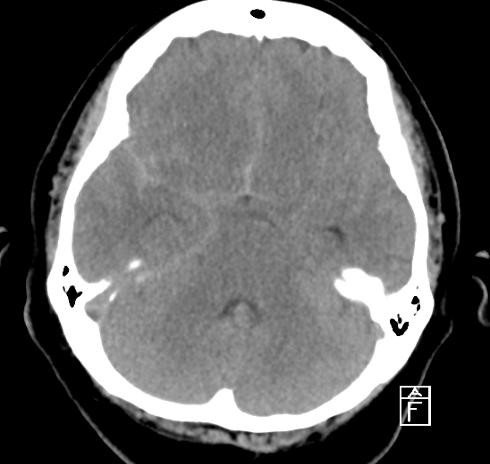

Case 6: A 12-year-old boy presents with nausea, vomiting, and headache for 1 month. CT shows the following. What is the diagnosis?

Figure 18. Case 6’s CT of the head. Image courtesy of the Baylor Scott and White Memorial Hospital–Temple, Texas.

Answer: Hydrocephalus